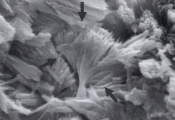

Рис. 3. Сканированная электронная микрофотография поверхности кальция оксалата, удаленного из мочевого пузыря 10-летнего кастрированного самца кота. Обратите внимание на сульфадиазиновый кристалл веерообразной формы (увеличение Х 2,880). |